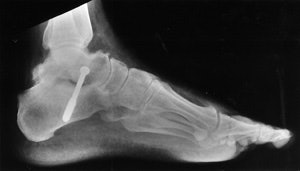

In 96 patients evaluated for arthritis pain, 218 joints were injected (figure 1).

FIGURE 1. (A) Lateral radiograph of a patient with hindfoot pain and the suggestion of subtalar arthrosis.

(B) Sagittal fat-suppressed MR image showing posterior facet arthrosis of the subtalar joint and edema within the sinus tarsi.

(C) The patient undergoing a series of injections with contrast seen in the ankle and sinus tarsi. The ankle injection did not relieve symptoms, the sinus tarsi injection relieved 75% of pain.

(D) Lateral radiograph 10 months after talo-calcaneal fusion and excision of the sinus tarsi contents with a reported 80% reduction in pain.

All joints were injected successfully. Based upon the degree of pain relief from injection, 22 patients were offered surgical treatment and 18 people chose surgical treatment. There were 7 painful ankles and 11 painful feet in 18 patients that had surgical treatment. All of the painful small joints of the foot had arthrodesis, 3 of the painful ankles had arthrodesis, 2 ankles had synovectomy and 2 had replacement arthroplasty. Ten of 11 patients with foot arthrodesis had pain relief similar to that of the injection and 1 patient had approximately 50% pain relief.

The ability to limit the number of joints fused by assessing pain relief from a series of preoperative image-guided arthrograms was also important. All patients have a minimum of 9 months follow-up since surgery. Five of 7 ankle pain patients had relief similar to the injection; one ankle arthroplasty and one arthrodesis patient had 50% improvement, none were worse following surgery. All surgical pathology specimens from the arthrodesis sites demonstrated the pathologic tissue changes of chronic synovitis, degenerative joint disease (i.e., bone and cartilage degeneration), or both.